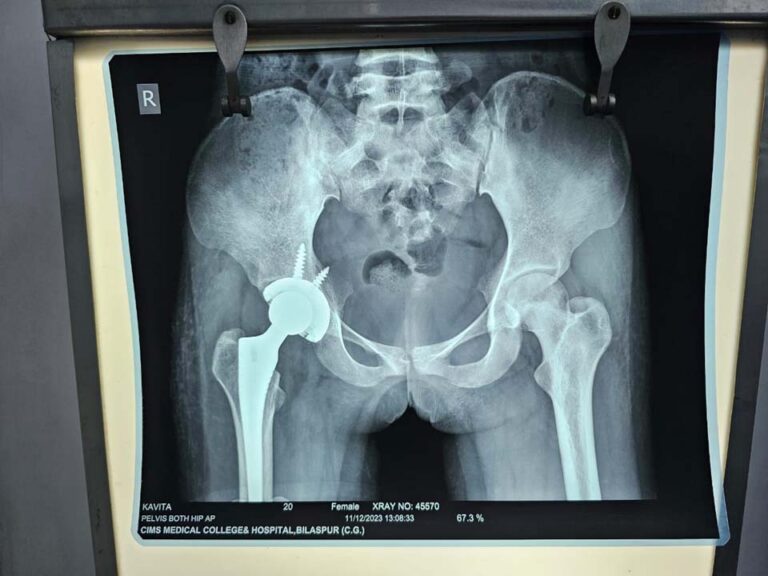

सिम्स में गरीब किसान की बेटी का सफल टोटल हिप रिप्लेसमेंट ऑपरेशन

प्रधानमंत्री जन आरोग्य योजना से हुआ निःशुल्क इलाज छत्तीसगढ़ रिपोर्टर बिलासपुर 18 जनवरी 2024। पामगढ़ ब्लॉक के एक गरीब किसान की बेटी का सिम्स अस्पताल में सफल टोटल हिप रिप्लेसमेंट सर्जरी किया गया है। प्रधानमंत्री जन आरोग्य योजना से लगभग ढाई लाख रुपए की सर्जरी के लिए उसे एक भी […]